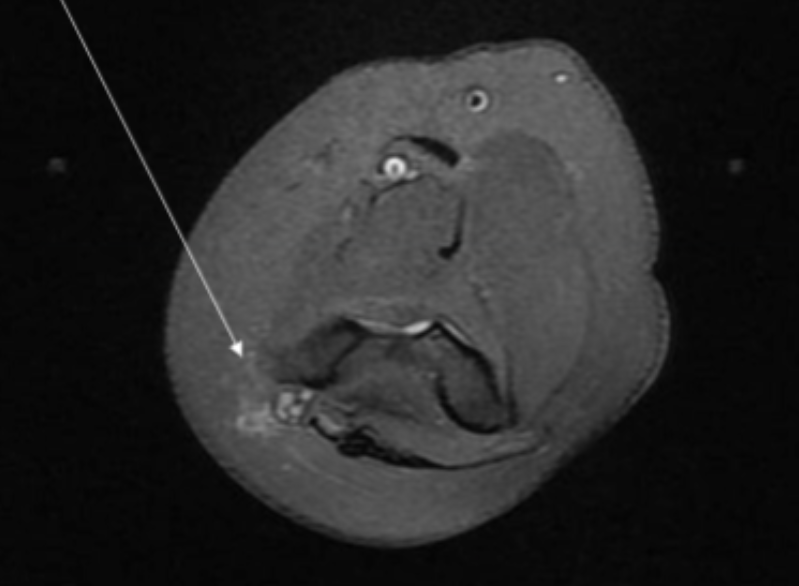

Describe the pathology indicated by the arrow (Ax PD).

Anterior talofibular ligament (ATFL) tear